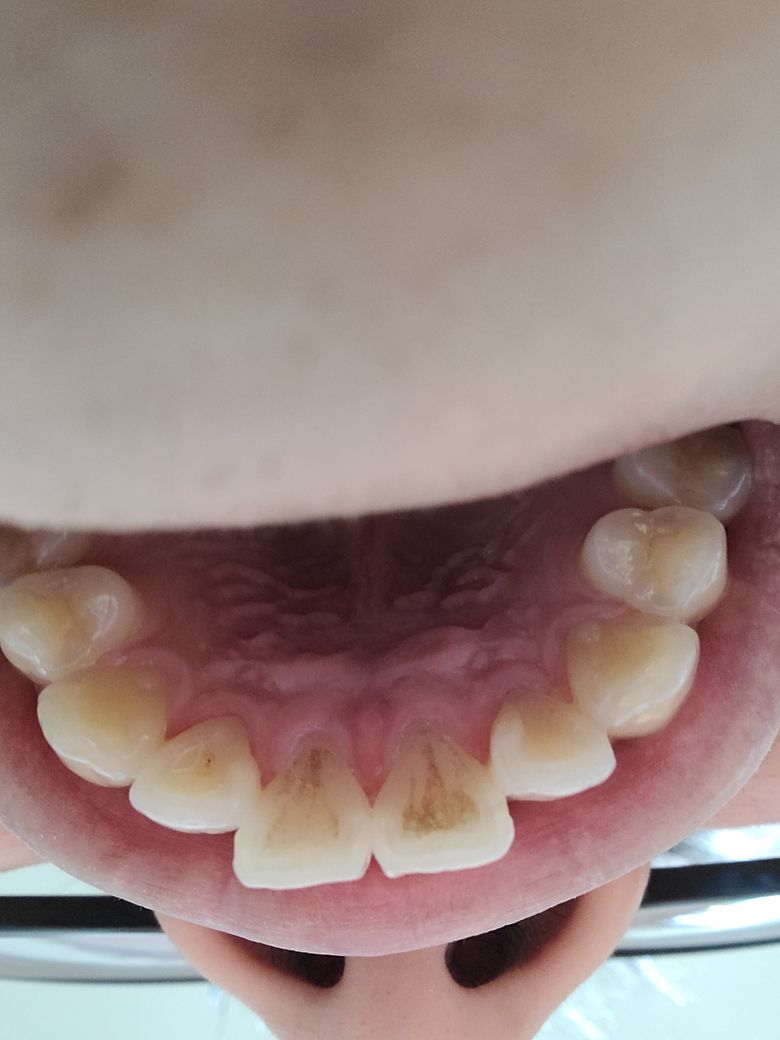

앞니 뒤쪽에 생긴 갈색은 충치인가요?

송곳니 쪽은 몇년전 충치치료를 받았는데요ㅠㅠ앞니 앞쪽에 갈색갈 뭔가가 생겼다가 양치질 세게 몇번 하면 사라지는게 몇차례 반복되서 찍어봤더니 저러네요..

현재 음식물로 인한 착색으로 보입니다. 치과에서 스케일링시 제거가 가능하기에 치과에 방문하여 진료를 받길 권합니다.

사진에 보이는건 충치가 아니고 차색이 되신거 같습니다. 커피나 흡연을 하시면 저렇게 착색이 됩니다.

착색된 치석입니다.

커피 흡연 검은색음식 등 섭취하실경우

생길 수 있으며

양치로는 제거 불가능합니다

치과에서 스케일링으로 처리가능합니다.

사진상 충치라기보다는 착색, 변색에 가까운 것 같습니다. 식습관(특히 커피나 색소가 포함된 음료수)이나 흡연 등에 의해 치아가 착색될 수 있는데 스케일링으로 어느정도 제거가 가능합니다

보통 검은색 선으로 나타나는 것을 초기충치라 하는데 변색과 달리 긁혀 사라지지 않습니다.